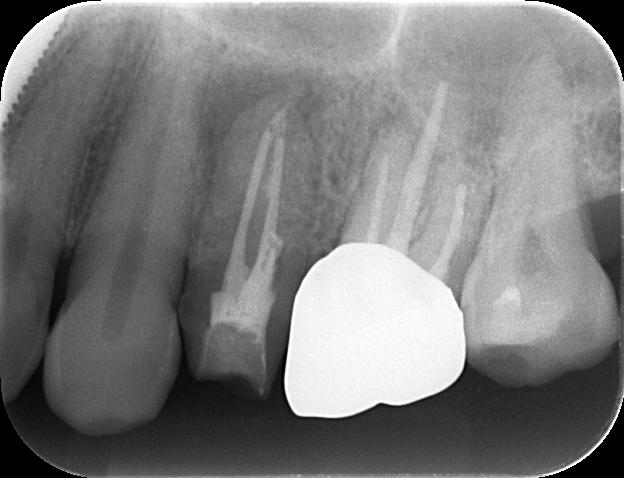

こちらの画像は、

MMデンタルクリニック東京院で行っている

歯科用拡大顕微鏡(マイクロ)を用いた

精密根管治療の様子 です。

従来の保険適用で行う根管治療では、

病巣の原因となっている

部位をレントゲンで確認します。

しかし、画像を比較して頂ければ一目瞭然ですが、

治療の精度には大きな差があります。

保険の根管治療では、非常に小さな根管内部を

肉眼と手の感覚を頼りに治療するため、

歯の中の細菌を多く取り残したりして

再度の治療が必要になる

可能性が高いのが現実です。